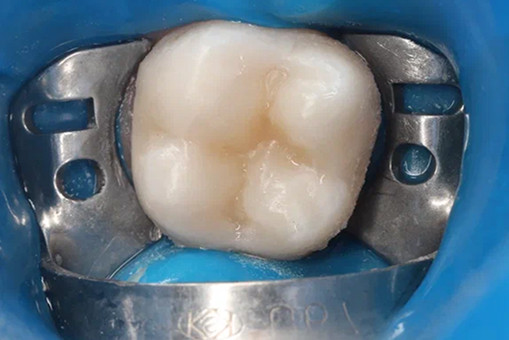

В нашей клинике лечение кариеса проводится по всем мировым стандартам с использованием коффердама, под увеличением, делаем фотопротокол, местную анестезию (при необходимости общую или ЗАКС).

Лечение кариеса проводится следующим образом - сбор анамнеза, проведение местной анестезии, дентальный снимок (при необходимости), изоляция (коффердам), фотопротокол, удаление кариозных тканей (с использованием бора), антисептическая обработка полости, реставрация пломбировочным материалом, шлифовка, полировка.

До/после лечения